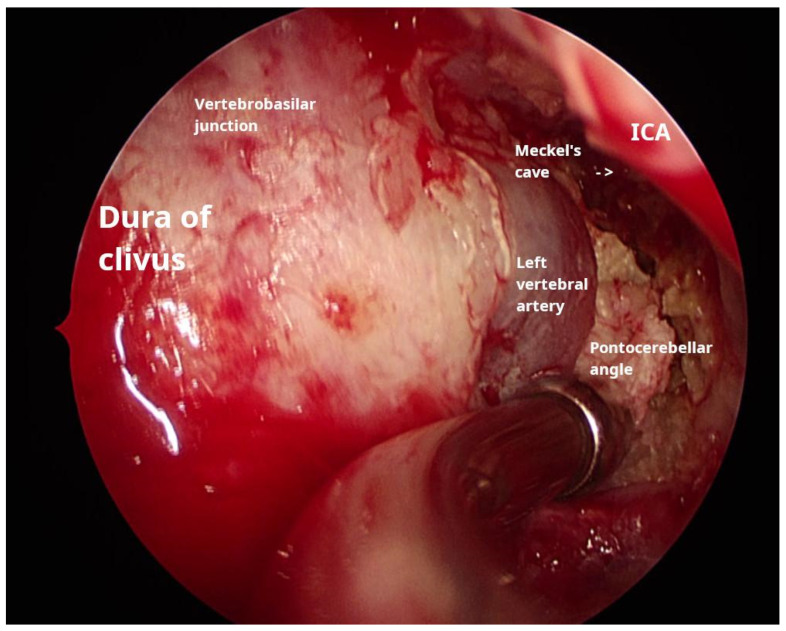

Background and Clinical Significance: Petrous bone cholesteatoma is a rare and complex condition that poses significant challenges in terms of its diagnosis and treatment. This benign yet locally aggressive lesion can cause extensive destruction of the surrounding structures, potentially leading to serious complications. Case Presentation: We present a case of extensive petrous bone cholesteatoma involving nearly the entire skull base. High-resolution CT and MRI were used to assess the extent of the lesion and its relationship with critical neurovascular structures. The cholesteatoma extended from the petrous apex to the clivus, involving the internal auditory canal and Meckel's cave, encasing the internal carotid artery, and compressing the brainstem. The surgical strategy included combined endoscopic transsphenoidal and transclival techniques with a retrolabyrinthine approach. The endoscopic component provided access to the anterior and central skull base regions, whereas the retrolabyrinthine approach allowed us to gain access to the posterior petrous area. Careful dissection was performed to separate the cholesteatoma from the internal carotid artery and the brainstem. Neuromonitoring was performed throughout the procedure to ensure cranial nerve integrity. This combined approach enabled gross total resection, and postoperative imaging confirmed successful tumor removal. The patient's recovery was uneventful, and no new neurological deficits were observed. Conclusions: The successful management of this complex case demonstrates the efficacy and safety of combining endoscopic surgical approaches for extensive skull base cholesteatomas. This multi-corridor approach allows for maximal tumor resection while also minimizing the risks to critical neurovascular structures.